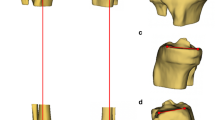

All measurements were done on three-dimensional CAD models, which were generated on the basis of individual CT-scans, including the hip, knee, and ankle center. Measurements included the MPTS, LPTS, and the MPTA. For measuring the MPTS and LPTS, first, the mechanical axis of the tibia was established using the ankle center. The patient’s individual slope was defined as the line tangent to the most prominent aspects of the anterior and posterior cortices of the respective compartment. The angle between the plane perpendicular to the mechanical axis of the tibia and the patient’s individual slope was measured and defined as the patient’s medial or lateral slope angle. MPTA was defined as the angle between the tibial mechanical axis and the proximal articular surface of the tibia in the coronal plane. To investigate if there are significant differences of MPTS, LPTS, and MPTA in gender or in alignment, variations have been evaluated respectively. To quantify the fraction of patients for whom the use of a standard technique would lead to an altered MPTS, LPTS, or MPTA > 2°, the patients’ data were compared to those of standard techniques. For the PTS, a standard value of 5° was used and the respective fraction of patients having an MPTS or LPTS < 3° or > 7° was determined. Concerning MPTA, a value of 90° was used for mechanical alignment, while a value of 87° was used for anatomical alignment and the fraction of patients was determined who had an MPTA < 88° or > 92°, and < 85° or 89°, respectively.

Analysis showed that 65% (152/234) of patients had an MPTS, and 53% (124/234) of patients had a LTPS < 3° or > 7°, which would result in an alteration of the patient’s PTS by more than 2° if a standard PTS of 5° was used (Figs. 1 and 2).